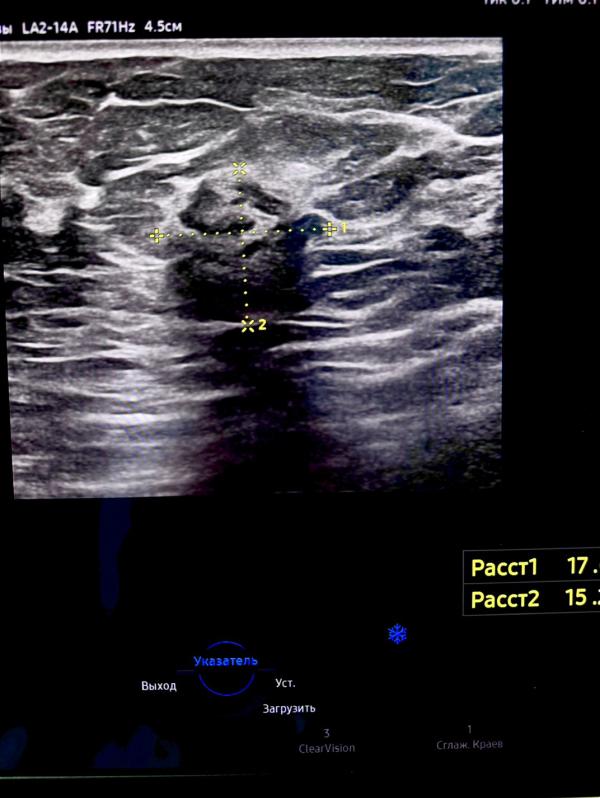

ЗНО левой молочной железы у женщины 44 лет: что это значит, результаты проф. осмотра и дальнейшие действия?

Женщина 44г , проходила проф осмотр, жалоб никаких не предъявляет!

Заключение: ЗНО левой молочной железы!🙏🏻